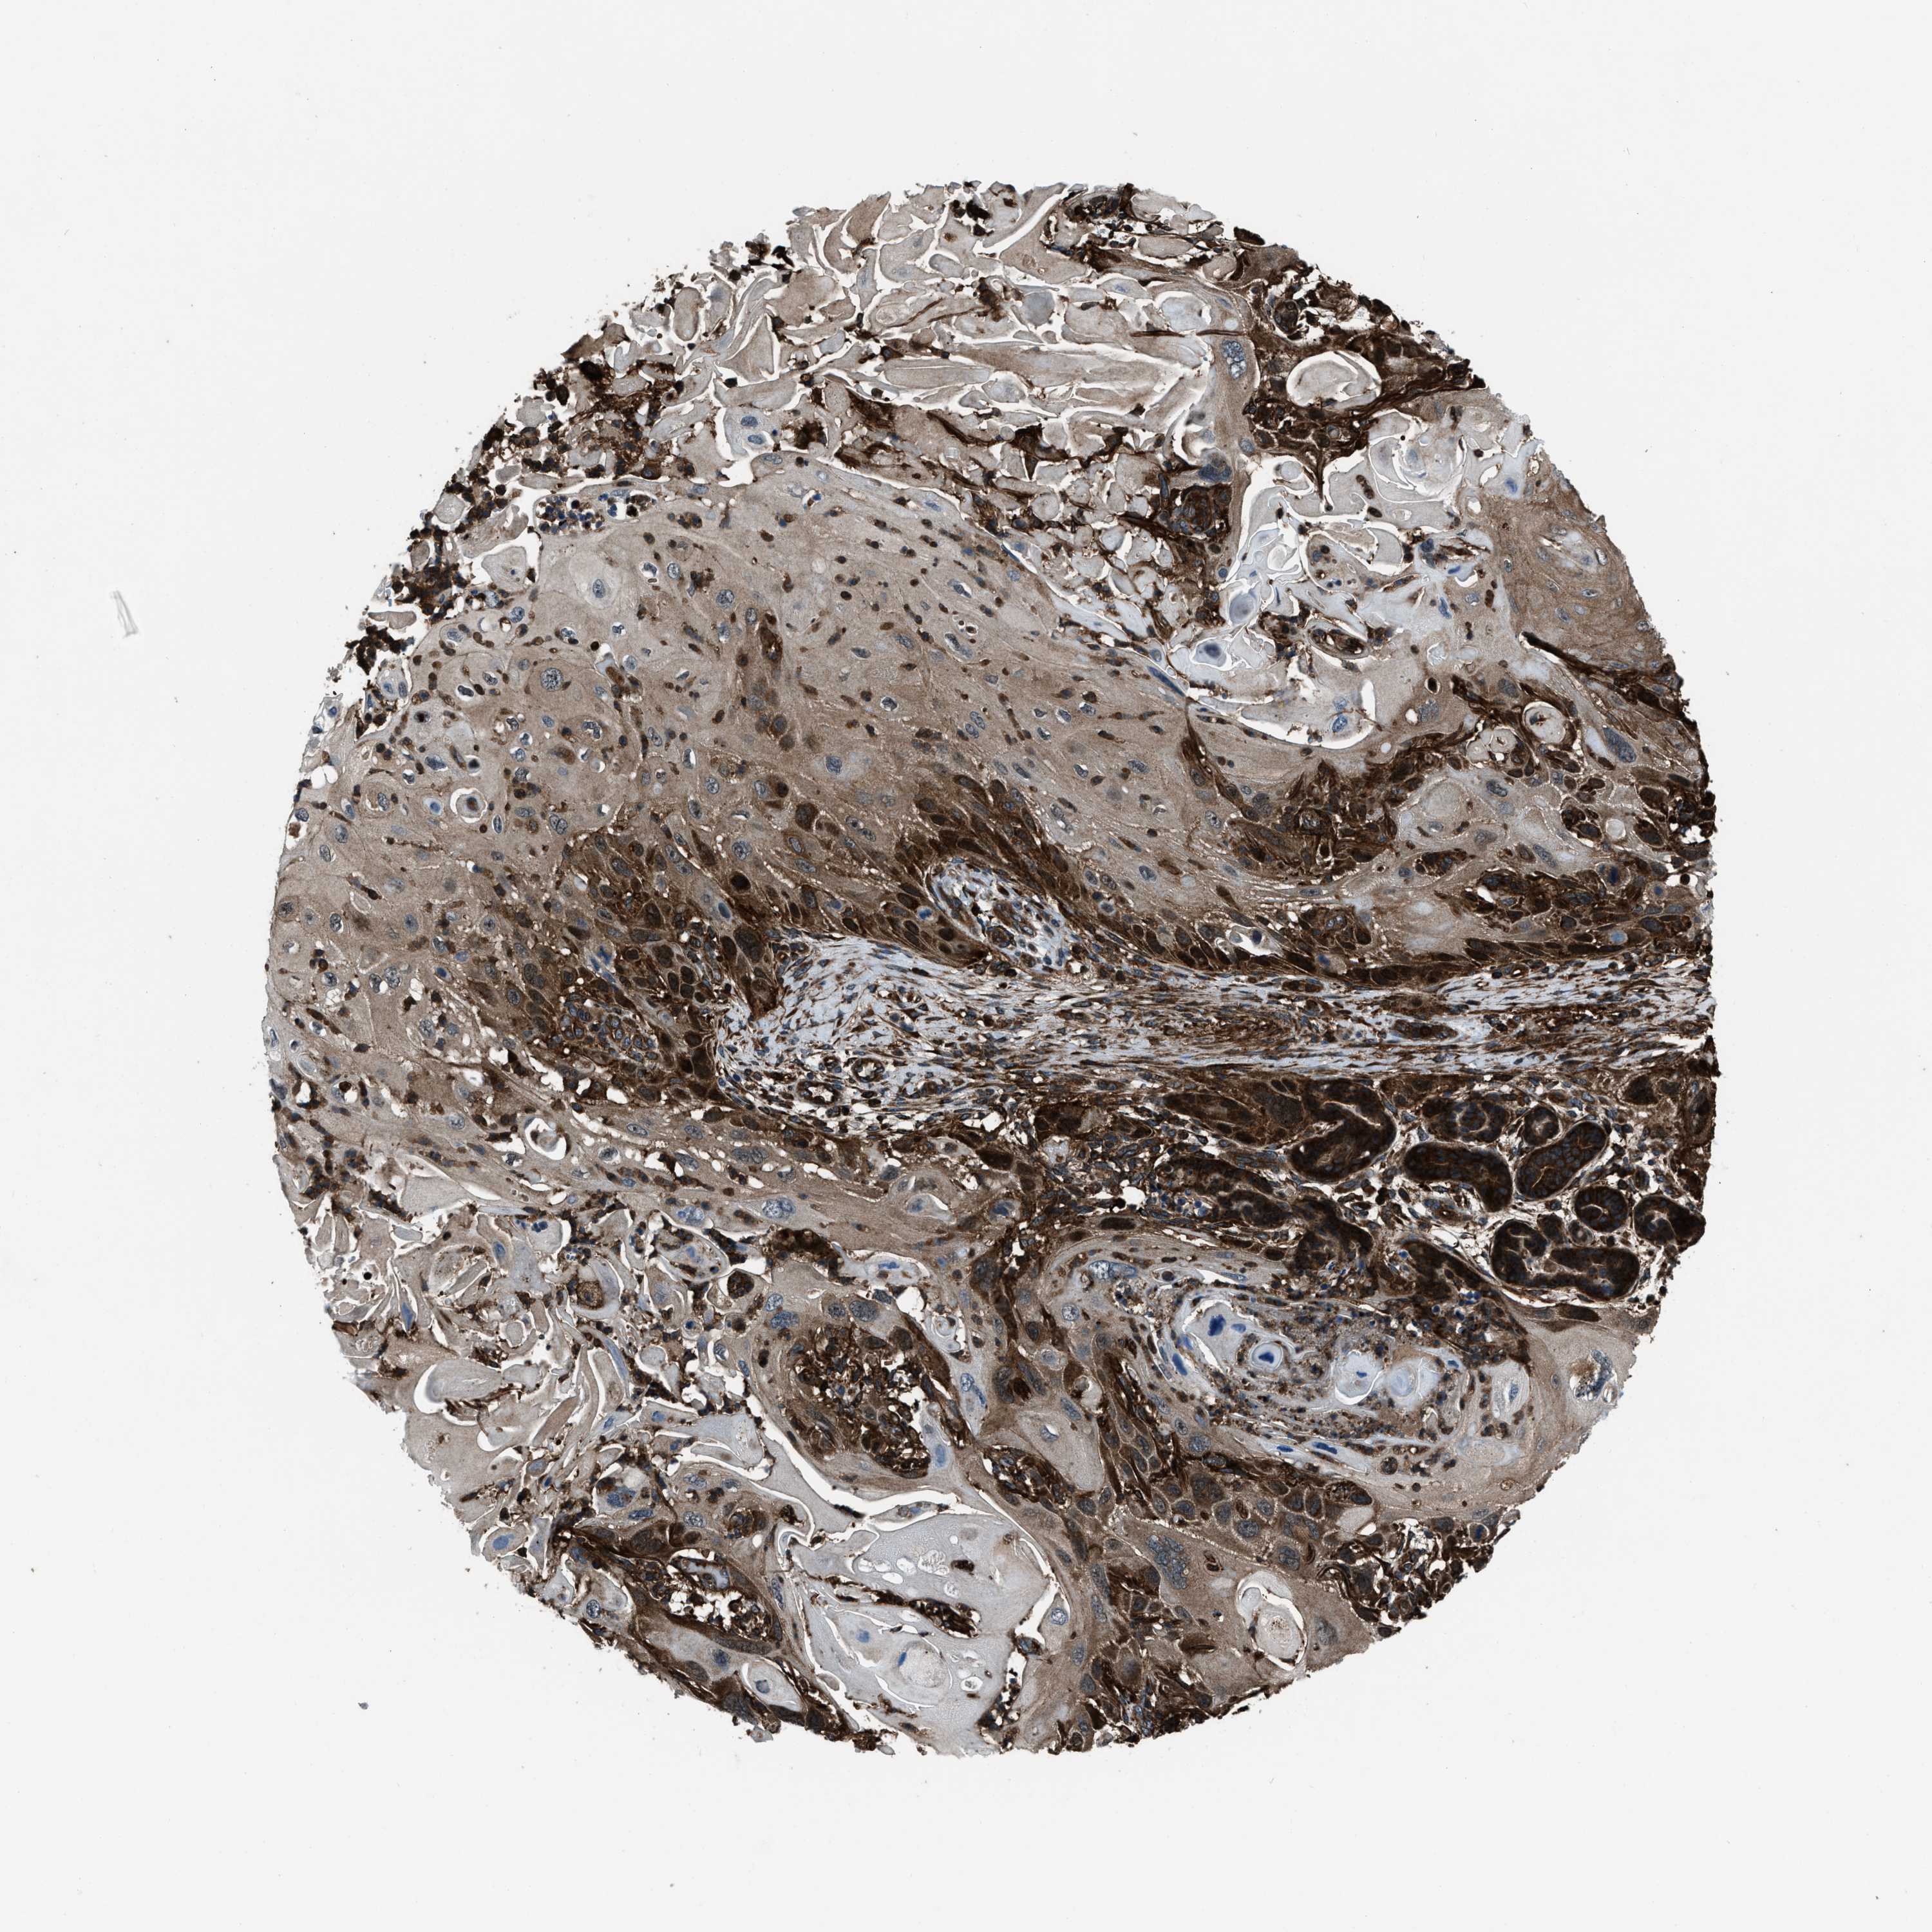

Basal cell and squamous cell cancer

SKIN CANCER - Protein expressioni

A mouse-over function shows sample information and annotation data. Click on an image to view it in a full screen mode. Samples can be filtered based on level of antibody staining by selecting one or several of the following categories: high, medium, low and not detected. The assay and annotation is described here.

Each image is clickable and will lead to virtual microscopy that enables deeper exploration of all samples and also displays staining intensity scores, fraction scores and subcellular localization as well as patient and tissue information for each sample.

Antibody HPA019346

Staining

High

Strong

>75%

Location

Cytoplasmic/membranous

Squamous cell carcinoma, NOS

Squamous cell carcinoma, metastatic, NOS